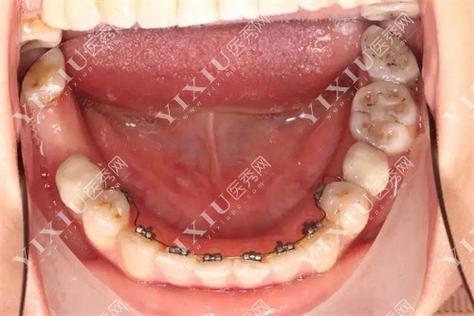

舌侧矫正调整咬合的原理,依托于数字化技术与个性化方案设计,与传统唇侧矫正不同,舌侧托槽体积更小、形态更贴合牙齿内表面,需通过口内扫描获取牙齿数据,结合3D打印技术制作个性化托槽和弓丝,医生在设计方案时,会重点分析患者的咬合轨迹、牙尖交错位及下颌运动范围,通过模拟牙齿移动路径,逐步调整牙齿的倾斜度、转矩及垂直高度,最终实现上下牙弓的匹配,针对深覆合(上牙覆盖下牙过多),舌侧矫正可通过压低上前牙或伸长下后牙,改善垂直向咬合关系;对于反颌(“地包天”),则通过内收下前牙或推进上前牙,调整水平向咬合偏差,这种“精准到每颗牙”的控制力,使得咬合调整更符合个体生理功能需求。

与传统唇侧矫正相比,舌侧矫正在咬合调整中具有显著优势,传统矫正的托槽位于唇侧,力量传递易受口腔软组织干扰,且对牙齿转矩的控制精度有限,尤其在复杂咬合问题(如扭转牙、长轴倾斜)的调整中可能出现偏差,而舌侧矫正因托槽粘接在牙齿内侧,远离面部肌肉和唇颊软组织,减少了外力干扰,且通过个性化弓丝的弯制,可实现牙齿在唇舌向、近远中向及垂直向的同步移动,确保咬合接触点的均匀分布,舌侧矫正的数字化设计能提前预测咬合重建后的效果,避免传统矫正中可能出现的“咬合过高”“咬合干扰”等问题,降低颞下颌关节的适应负担。